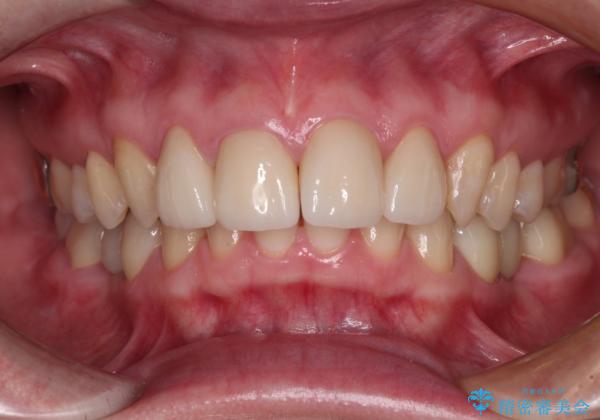

継ぎ接ぎだらけの上顎前歯もオールセラミッククラウンにて審美的に改善したいとのことでしたが、捻れが強くあるため、事前に矯正治療で歯列を整えてから、補綴治療を行うこととしました。

目立つ部分の銀歯や気になる変色歯をまとめてきれいに仕上げることができました。